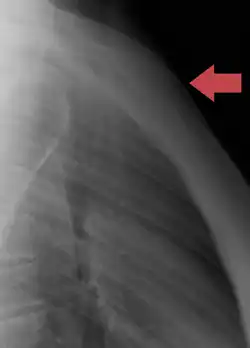

Traumatologie

Les fractures du sternum sont plutôt rares. Elles peuvent résulter d'un traumatisme, par exemple lorsque la poitrine d'un conducteur est forcée dans la colonne de direction d'une voiture lors d'un accident de la route. Une fracture du sternum est généralement comminutive. Le site le plus courant des fractures sternales se situe à l'angle sternal. Certaines études révèlent que des coups de poing répétés ou des coups continus dans la région du sternum ont également causé des fractures, comme dans des sports de contact comme le hockey et le football. Les fractures du sternum sont fréquemment associées à des lésions sous-jacentes comme des contusions pulmonaires[7].